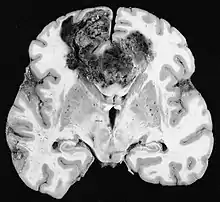

Glioblastome

Les tumeurs des cellules gliales les plus courantes et les plus malignes sont les glioblastomes. Ils consistent en une masse hétérogène de cellules d'astrocytome peu différenciées principalement chez l'adulte. Ils surviennent généralement dans les hémisphères cérébraux, plus rarement dans le tronc cérébral ou la moelle épinière. Sauf dans de très rares cas, comme toutes les tumeurs cérébrales, elles ne s'étendent pas au-delà des structures du système nerveux central.

Le glioblastome peut provenir d'une forme diffuse (II. grade) ou un astrocytome anaplasique (III. grade) développer. Dans ce dernier cas, il est dit secondaire. Cependant, lorsqu'elle survient sans antécédent ni signe de malignité antérieure, on parle de maladie primaire. Les glioblastomes sont traités par chirurgie, radiothérapie et chimiothérapie. Ils sont difficiles à guérir et rares sont les cas qui survivent au-delà de trois ans.

Les métastases cérébrales sont les néoplasmes intracrâniens les plus courants chez les adultes, étant dix fois plus fréquents que les tumeurs cérébrales primaires. Ils marchent à 20 jusqu'à 40 pour cent des adultes atteints de cancer et sont principalement associés au cancer du poumon et du sein et au mélanome . Ces lésions résultent de la propagation des cellules cancéreuses dans la circulation sanguine et surviennent le plus souvent à la jonction de la matière grise et blanche, où la section transversale des vaisseaux sanguins change, emprisonnant les embolies de cellules tumorales . 80 % des lésions surviennent dans les hémisphères cérébraux, 15 pour cent dans le cervelet et 5 pour cent dans le tronc cérébral. Environ 80 % des patients ont des antécédents de cancer systémique et 70 pour cent ont de multiples métastases cérébrales.